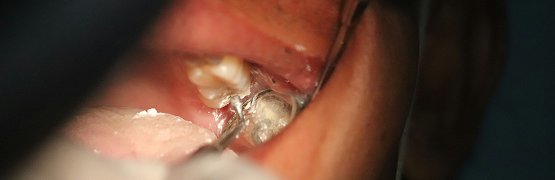

Auch wenn kein neues Amalgam mehr verwendet werden darf, bleibt die Entfernung bestehender Amalgamfüllungen weiterhin eine Aufgabe in Zahnarztpraxen. Hinzu kommen die Ausnahmen, in denen eine Amalgamfüllung noch medizinisch indiziert sein kann. Um Patienten, Ihr medizinisches Fachpersonal und sich selbst zu schützen, sind Schutzmaßnahmen für die Arbeit mit dem quecksilberhaltigen Material nötig.

• Arbeiten Sie mit Amalgam nur in gut durchlüfteten Räumen und nutzen Sie leistungsfähige Absaugmaterialien, um mögliche Quecksilberdämpfe unmittelbar an der Quelle zu erfassen.

• Verarbeiten Sie Amalgam nur mit Kofferdam, um Partikel im Behandlungsumfeld fernzuhalten.

• Der Einsatz von Kühlmitteln ist sinnvoll, um die Dampffreisetzung zu verringern.

• Nutzen Sie spezielle Schutzmasken, welche Zahnärzte und ZFAs zusätzlich schützen.